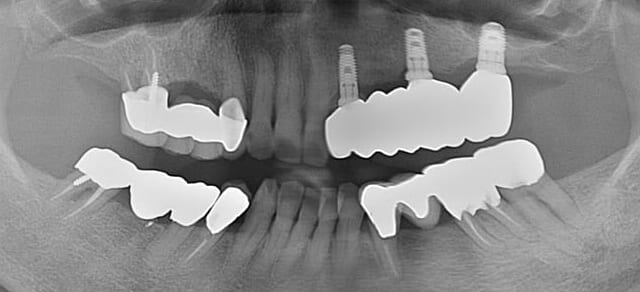

治療前

インプラントを6本入れるのではなく、インプラント3本(土台)の上に上部構造としてセラミックの歯(5本)をブリッジにする、インプラントブリッジをご提案しました。

CT撮影と精密なシミュレーションにより、インプラント治療は問題なく終わり、痛みや腫れもほとんどなく大変喜んでいただきました。